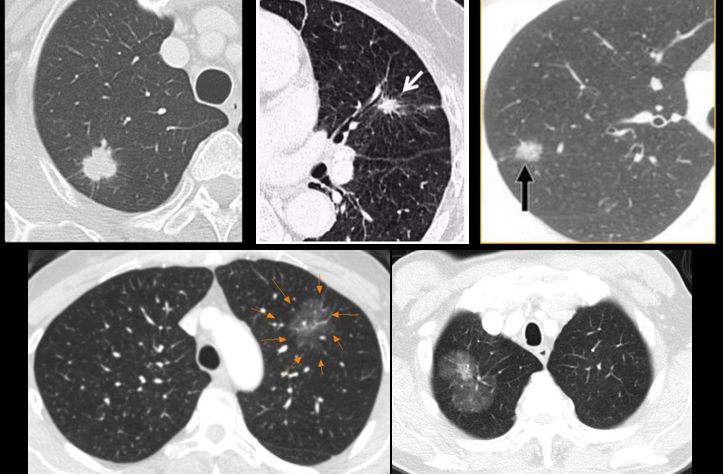

唐小军教授提到,直径≤8mm的结节需定期随访,是否需要手术要根据随访结果而定。对此,唐小军教授展示了几个具体的病例进行说明:

7mm磨玻璃结节,定期复查,20个月后CT发现结节长大,手术切除,病理证实为微浸润腺癌。因此,唐教授特意提醒大家,虽然磨玻璃结节50%以上为恶性,但也无需过分恐慌,因为其生长速度很慢,绝大多数小于7mm的磨玻璃结节均属很早期,可以定期复查,如果发现结节长大或密度增大,再手术切除。

磨玻璃结节,定期复查,5年均未见明显变化,继续随访。对于这种不生长的情况,专业称为“休眠”,休眠状态通常不需要手术治疗,患者可以带结节生活,因此,是否需要手术需要医生根据实际情况做专业判断。

8mm磨玻璃结节,定期随访,CT发现结节实性成分增多,手术切除,病理为腺癌。

8mm以上的结节,如果有典型的恶性特征,例如短毛刺、分叶等,要直接手术。唐小军教授强调,一旦发现这种情况,大多数无需做穿刺活检确认,要保证宁可错杀不能漏掉,但如在极少数特殊情况下,也可进行穿刺确认。